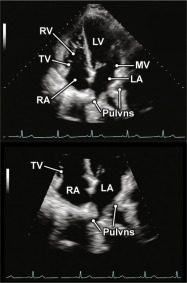

| 2.23. Mặt cắt 4 buồng từ mỏm khu trú vào các tĩnh mạch phổi |

Cửa sổ siêu âm từ mỏm tim

Mặt cắt 4 buồng Tối ưu hóa hình ảnh để khu trú vào nhĩ trái và các tĩnh mạch phổi |

Các tĩnh mạch phổi (Pulvns) Nhĩ trái (LA) Van hai lá (MV) Thất trái (LV) Nhĩ phải (RA) Van ba lá (TV) Thất phải (RV) |